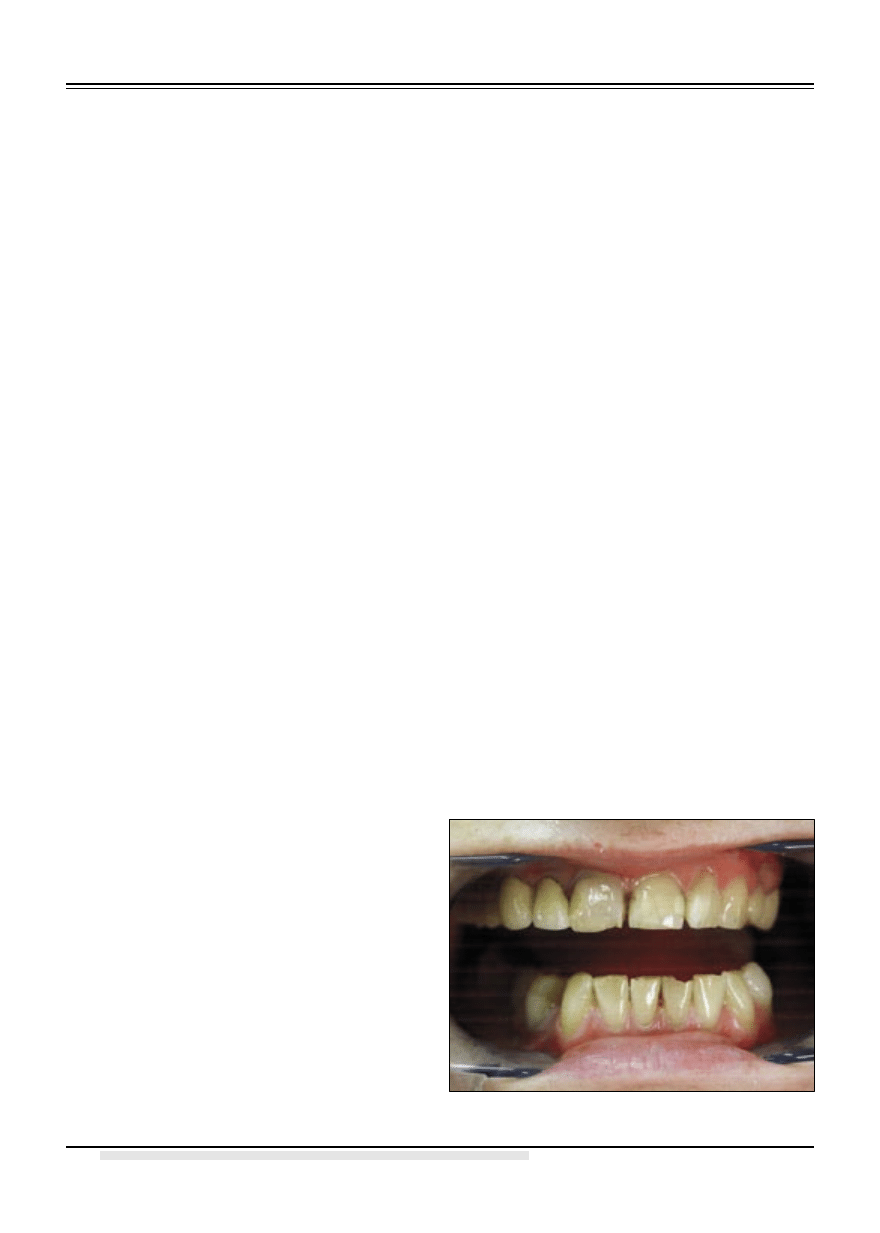

24, ząb 27. W żuchwie brak zębów 35, 36, 37, 46.

(ryc. 2)

Ryc. 2. Zdjęcie pantomograficzne.